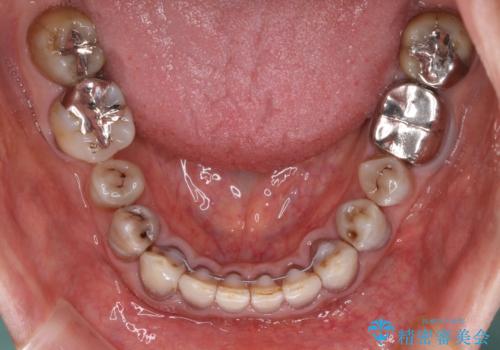

- 前歯のクロスバイトを気にして来院された患者様です。

骨格的に下顎が前方位ではありますが、歯並びが改善されれば正常咬合となることが分かったため、インビザラインを用いて咬み合わせを改善していくこととしました。